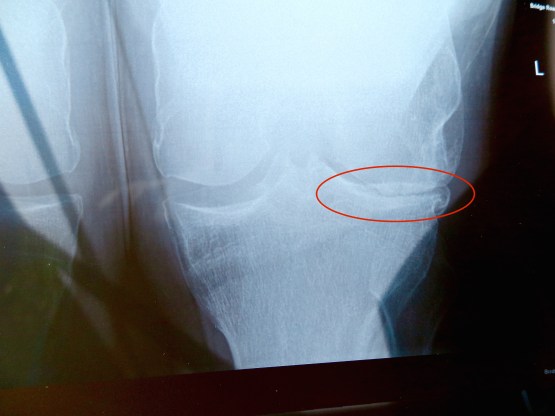

Yes. My left knee. And the mighty muscle groups of my thundering hams (att. G. Ainsworth), visible in this new (to me) form of imaging.

Does that look it needs a replacement? I asked the radiologist. Mmmm, she said nodding sagely, not much daylight there.

I have had trouble with my knees since my early teens. ‘Long-jumping into hard pits’ was one causative diagnosis. Sore knees stopped me playing football for what I like to think would have been the pinnacle of my glory days. I had my first (of three) athroscopies of the knee more than 30 years ago. (Arthroscopies: key hole surgery of the knee to tidy up tears in the cartilage surface and remove floating pieces, now widely discredited in terms of impact and usefulness.) An osteopath looking through my history recently found the first reference to knee pain in 1991. Lately, coming down mountains, not going up so much, the grind of bone on bone is so tangible that I imagine I can hear it, and sometimes I can.